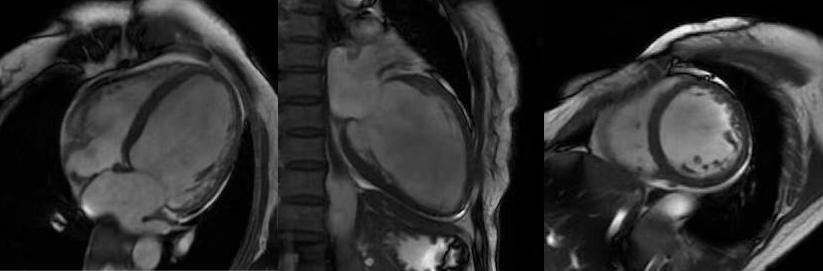

心臟磁共振被稱為心臟“一站式”檢查,通過(guò)多參數(shù)成像能夠?qū)π呐K的結(jié)構(gòu)、功能、室壁運(yùn)動(dòng)、心臟瓣膜、心肌灌注和活性進(jìn)行“一站式”評(píng)估。主要通過(guò)電影序列(短軸、兩腔心、四腔心、三腔心)、T2WI序列、首過(guò)灌注序列以及延遲強(qiáng)化序列對(duì)心臟進(jìn)行綜合成像。

缺血性心肌病:心臟磁共振可以評(píng)估心肌活性,心肌組織中失去活性的心肌細(xì)胞和延遲強(qiáng)化存在可靠的對(duì)應(yīng)關(guān)系,即失去活性的心肌組織有延遲強(qiáng)化,如急性心梗或急性冠脈綜合征、慢性缺血性心肌病。

右冠狀動(dòng)脈供血區(qū)透壁心梗伴心肌纖化

擴(kuò)張型心肌病